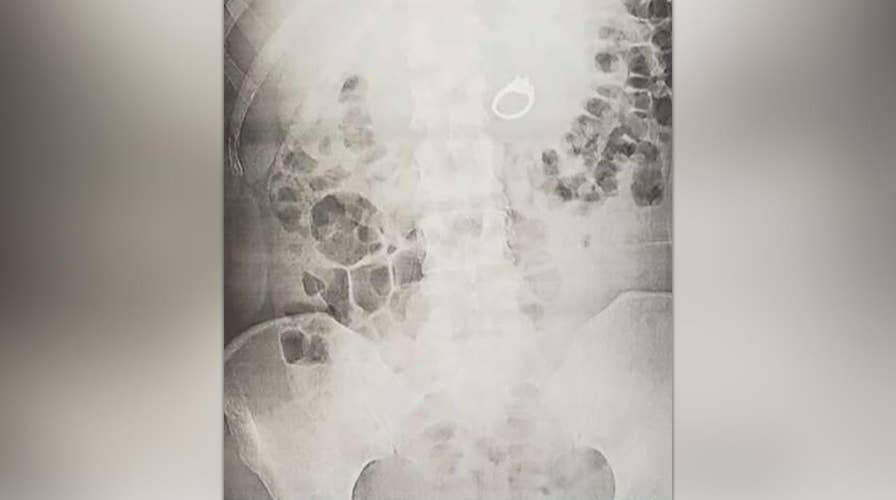

Jenna Evans says after dreaming that she swallowed her engagement ring to protect it she woke up to find that she actually had.